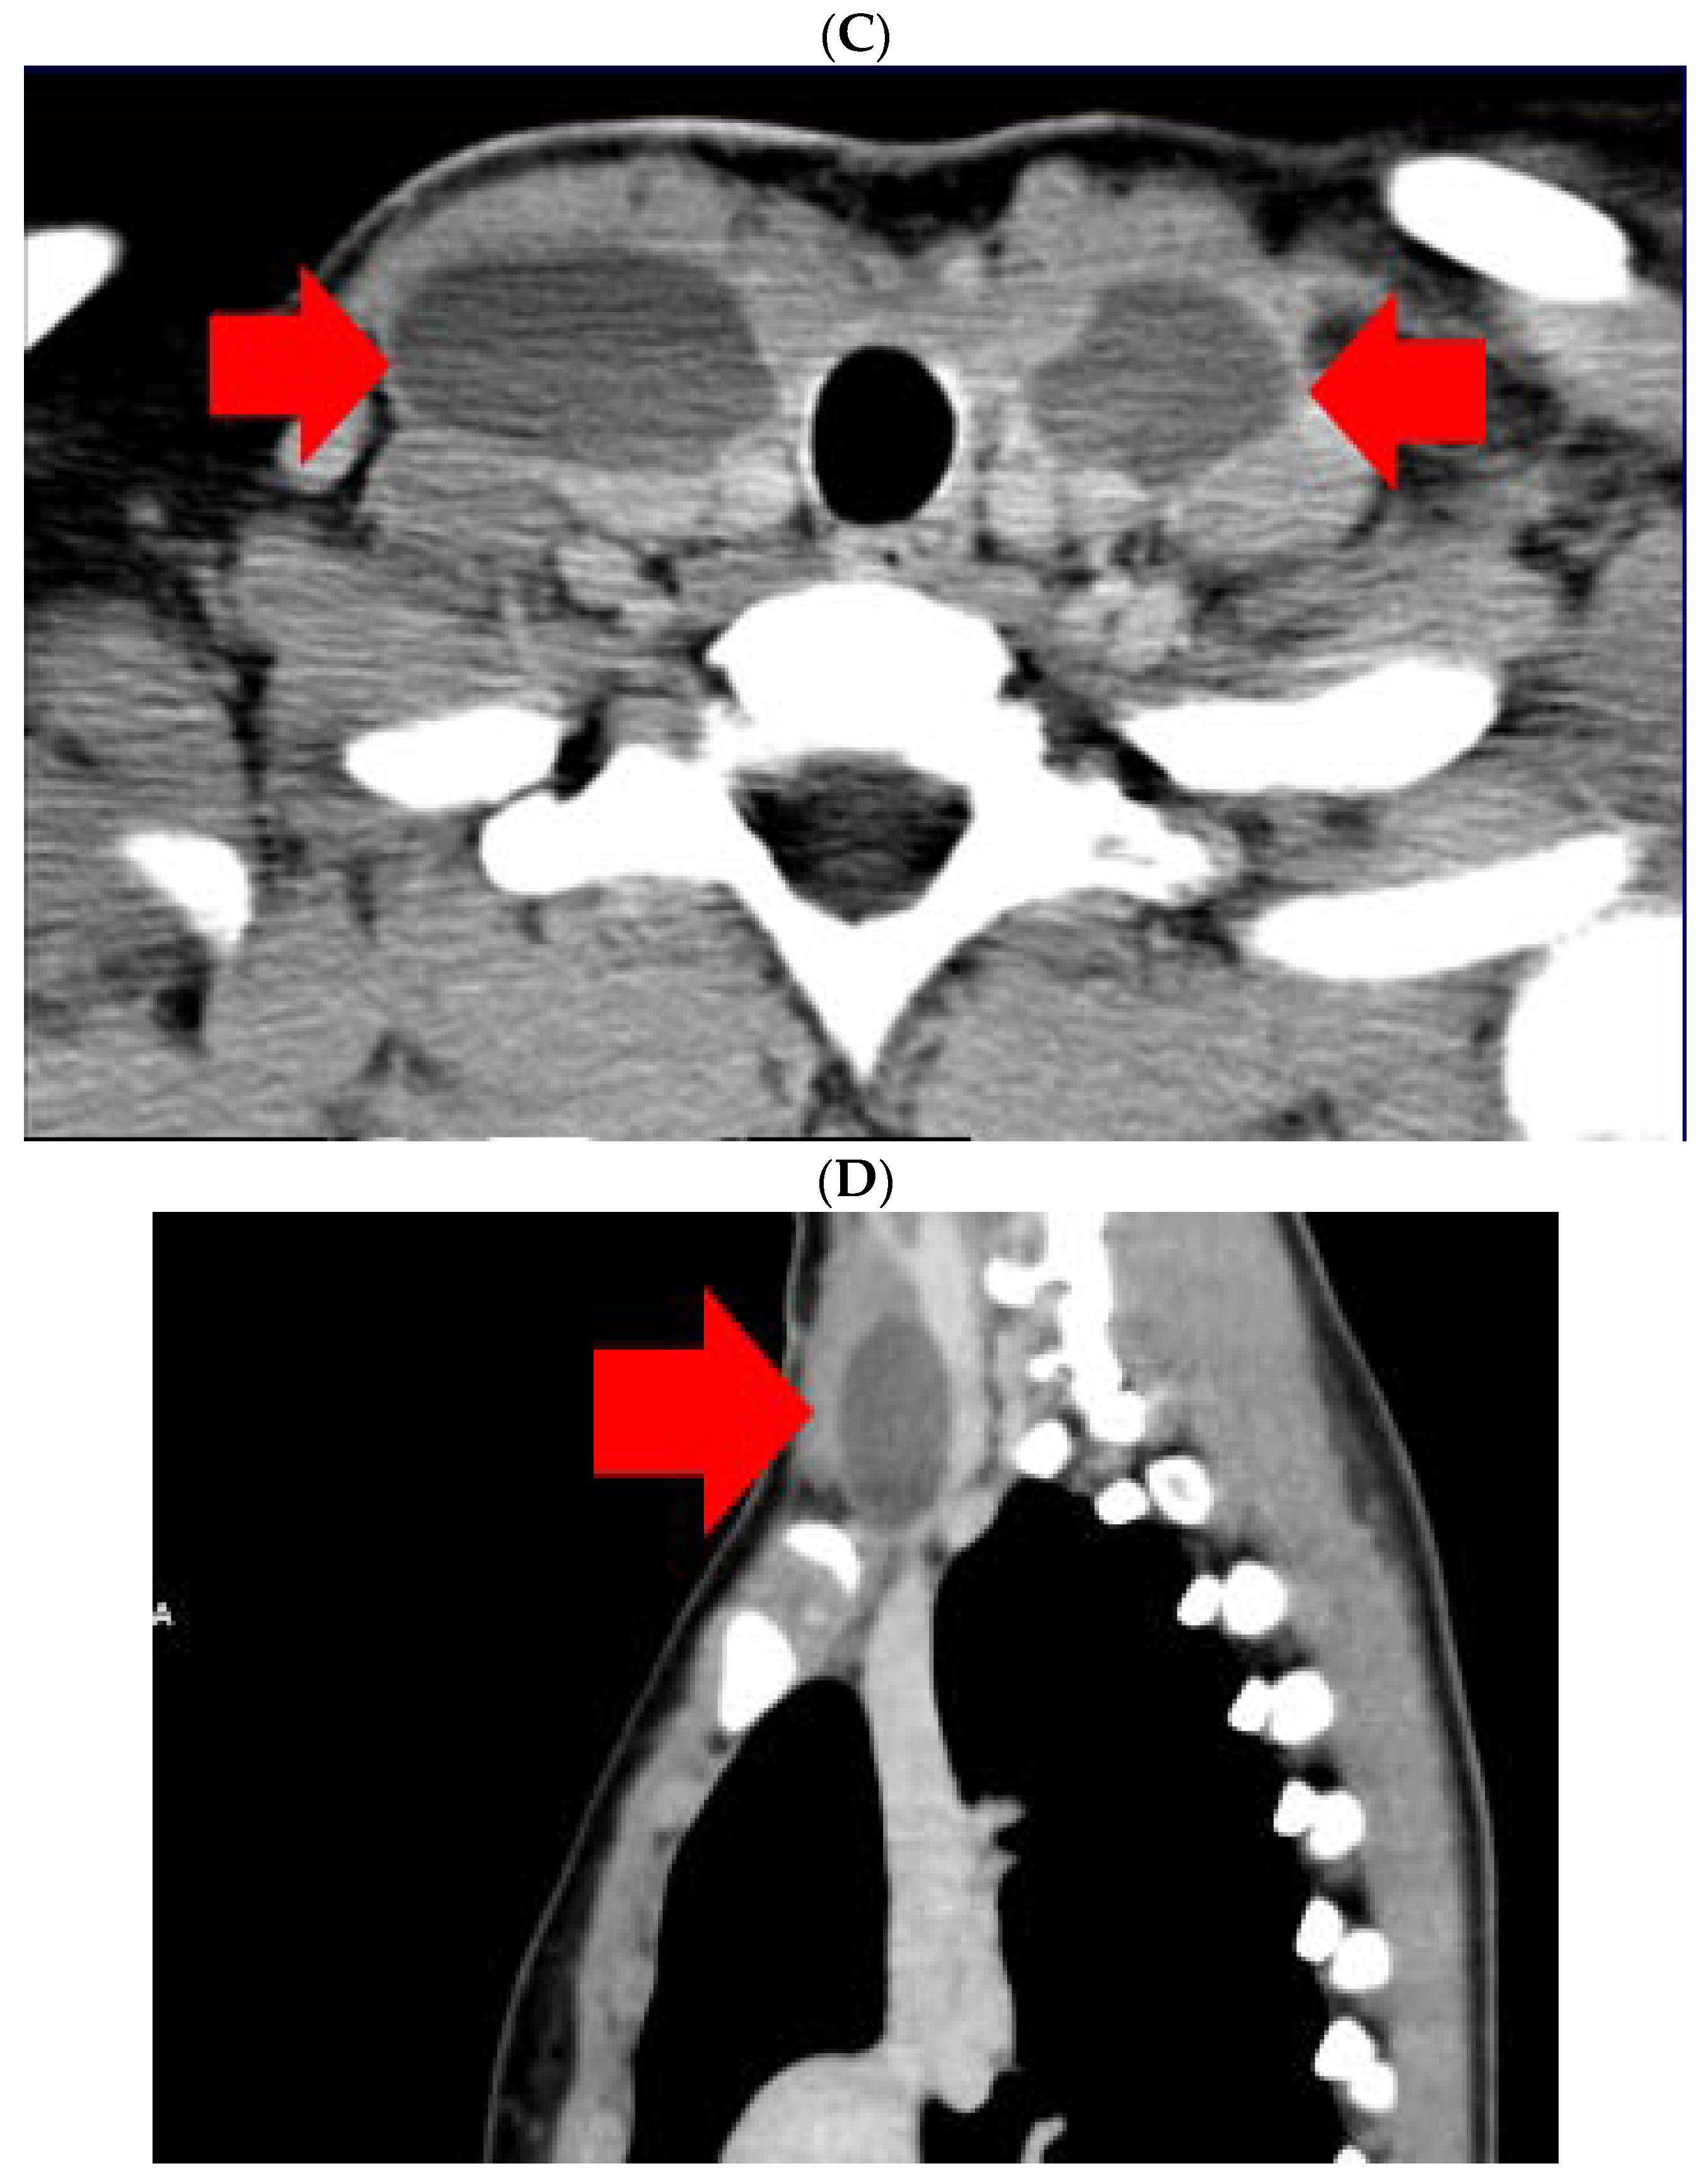

The diagnostic of HS was established after she was seen by different specialists as outpatient; she started local therapy with artificial tears and local nasal products with no significant improvement. In the meantime, a right neck swelling was progressively increasing, thus she was re-admitted 5 weeks since thyroidectomy. Neck ultrasound revealed a hypoechoic cystic-like area at the level of right lateral cervical level (of 60 mm maximum diameter) without thyroid remnants or local lymph node enlargement. (Figure 2).

Figure 2.

Neck ultrasound (right lateral area): hypoechoic, cystic- like, well-shaped mass of 6 by 2 by 4.5 cm (post-thyroidectomy capture: after 5 weeks since surgery before any additional intervention; red line represents the limits of the mass).

Ultrasound—guided fine need aspiration of the right mass provided cvasi-complete reduction of the liquid with stationary ultrasound features after 90 min. The liquid examination showed mature lymphocytes, rare erythrocytes, rare cholesterol crystals, lymph fluid, consistent with the diagnostic of lymphocele. A mild clinical improvement of HS—associated features was registered, but within 2 days, the neck mass rapidly regrew, and the patient was re-admitted. Under local anesthesia, there was a liquid evacuation (macroscopic aspect with milky-like aspect, a volume of 5–6 mL) and a drain tube was placed for 4 days. Ultrasound aspects showed a progressive regression of the right cystic mass with improvement of HS which slowly remitted within the next 2–3 months. (Figure 4).

Figure 4.

The evolution of within following weeks after thyroid surgery ultrasound features. (A). Right neck ultrasound aspect at the moment of fine needle aspiration (5 weeks since surgery)—on the right and 6 days after fine needle aspiration procedure (after cvasi-complete evacuation, the cystic mass relapsed within 48 h)—on the left. (B). Right neck ultrasound within the first day of tube drainage (6 weeks since initial surgery) showing a massive reduction of the cystic mass. (C). Drainage tube was removed after 4 days. Post-thyroidectomy scar and post-tube removal aspect. (D). Right neck ultrasound after 2 weeks from removing the drainage—persistent cystic mass, but with progressive improvement of HS (approximately 9 weeks since initial surgery). (E). Right neck ultrasound after another 2 weeks from removing the drainage –progressive reduction of cystic mass, but with remarkable improvement of HS (approximately 11 weeks since initial surgery). (F). Scar aspect 12 weeks since surgery and 5 weeks since lymphocele drainage. (G). Recovery of HS—approximately 8 weeks since drainage. (H1,H2). Bilateral neck ultrasound 20 weeks since thyroid surgery showing regression of the lesions on both sides versus prior examinations. (H1). Right later-cervical cystic collection of 2 by 2.8 by 0.9 cm (2.5 mL) and peripheral areas of fibrotic reorganization. (H2). Left later-cervical hypoechoic, inhomogeneous mass (no vascular signal) showing fibrotic reorganization (0.25 mL).